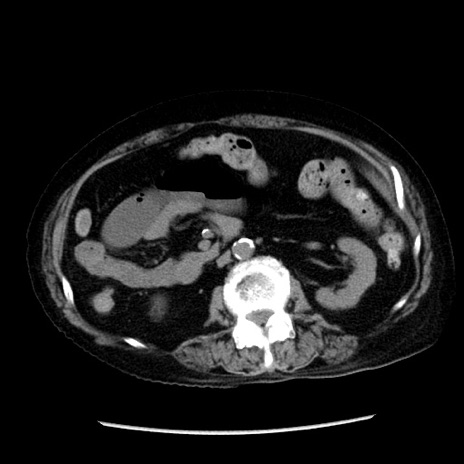

症例14(横断像)

【症例】 90歳代女性

【主訴】 腹痛・嘔吐

【現病歴】今朝から左側腹部痛を認めた。 経過観察していたが、嘔吐を認めたため来院。

【既往歴】 子宮癌術後

【身体所見】 意識清明、BP 127/54mmHg、P 98bpm Sp02 95%(RA)、BT 35.8°C、腹部平坦・軟腸ぜん動音聴取良好、右下腹部圧痛(+) 反跳痛なし

【データ】WBC 9800、CRP 0.46